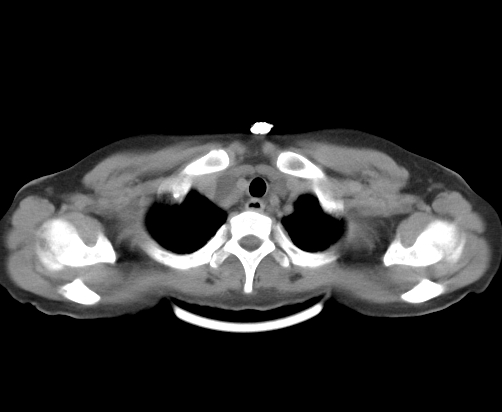

腹部平扫